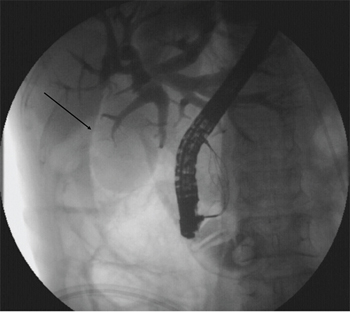

A 49-year-old female was admitted for persistent abdominal pain and fever of 1 week’s duration. MRCP showed multiple common bile duct stones with accompanying duct dilatation. After admission, antibiotics were administered and ERCP was performed the following day. After successful intubation, ERCP revealed choledochectasia with multiple stones (maximum diameter 1.6 cm × 1.5 cm). After routine EST, papillary sphincter dilatation was performed. Due to the larger size of the stones, lithotripsy and a stone-removal basket (Boston Scientific, Marlborough, MA, USA) were used to break and extract the stones. Repeat cholangiography demonstrated no residual stones; however, abnormal perinephric gas shadowing was observed (Figure 1). Under the duodenal endoscopy, an approximately 2.0 cm × 1.5 cm perforation was visualized on the lateral duodenal wall, with visible retroperitoneal loose connective tissue (Figure 2). We suspected that because the stone basket was over-rigid, it could have penetrated the contralateral intestinal wall due to inertial forces during stone removal.

Figure 1: Abnormal perinephric gas shadowing (arrow).